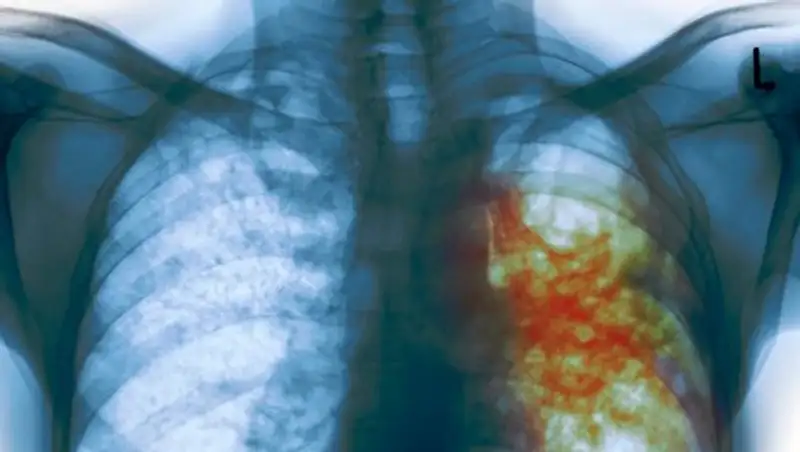

Важный антибиотик для больных муковисцидозом с синегнойной инфекцией будет внесен в перечень лекарственных средств для бесплатного обеспечения за счёт средств республиканского бюджета.

"Кроме того, министр поручил внести препарат колистин, жизненно важный антибиотик для больных муковисцидозом с синегнойной инфекцией, в перечень лекарственных средств для бесплатного обеспечения за счёт средств республиканского бюджета. От лица нашей организации хочу выразить глубокую благодарность Министерству здравоохранения Республики Казахстан и лично Елжану Амантаевичу за внимание к нашему заболеванию и поддержку наших больных детей", - написала Избасарова.